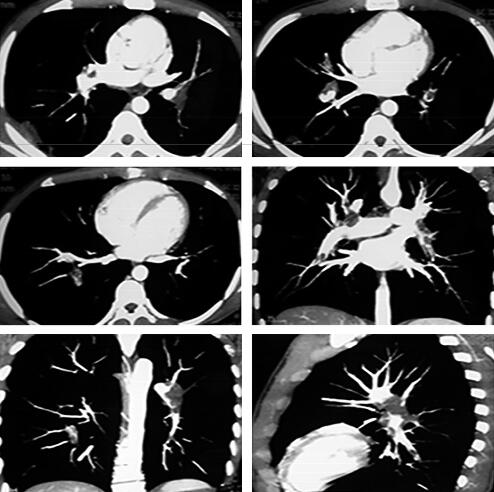

病情明显好转,肺栓塞三联征基本消失,2013年3月26日复查CTPA+双下肢CTV示:右肺中下叶肺动脉分支、左肺下叶肺动脉分支可见充盈缺损影,肺动脉的栓子负荷较前明显减少,双下肢静脉未见明显异常充盈缺损影,未见异常狭窄及扩张。右肺可见结节影、团片影,较前有所吸收好转(图5)。化验结果显示PT 31.7秒(9~13秒)、INR 2.65、D-二聚体500μg/L,提示抗凝有效并达标,建议患者继续口服华法林抗凝治疗。至此故事似乎该画上一个圆满的句号了,但临床实践总是没有想象中那么顺利。

图5

出院后患者规律口服华法林(双日2.5mg/d、单日1.25mg/d),于出院后第4天,再次发生咯血,为鲜红色,血量较病初增多,24小时可达50ml,并再次出现气短,当地医院给予对症处理(具体不详)并停用华法林,3天后患者因仍有少量咯血再次入我院。行胸部CT(2013年4月5日)显示双下肺新发磨玻璃样渗出影,将原有病灶掩盖,考虑为肺泡积血,纵隔窗显示右下肺空洞病灶基本同前(图6)。

图6

停用华法林观察1周,咯血和气短症状逐渐缓解,2013年4月14日复查胸部CT与2013年4月5日相比较,新发的磨玻璃影全部吸收,进一步证实为肺泡积血导致;而左肺下叶沿支气管走行斑片影、粟粒影与2013年4月5日比较明显吸收,原右下叶空洞较前进一步缩小(图7)。结合患者临床表现和影像学特征,考虑咯血原因为华法林药物副作用和(或)肺栓塞导致肺梗死所致,故改为低分子肝素皮下注射抗凝治疗。后咯血逐渐减少,出院后继续规律低分子肝素治疗。2013年5月22日患者门诊随访,无咯血,无气短,无胸痛,无发热,复查胸部CT示右下肺空洞基本吸收,遗留两个薄壁的小空腔及少许条索影(图8)。考虑患者为青年学生,久坐习惯可去除,规范低分子肝素皮下注射抗凝治疗总疗程3个月后停止抗凝。2013年10月16日复查CTPA提示未见肺动脉充盈缺损。

图7

图8